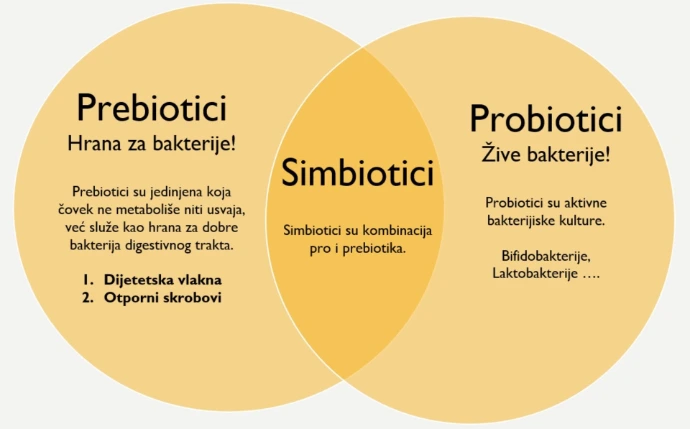

VRSTE PREBIOTIKA